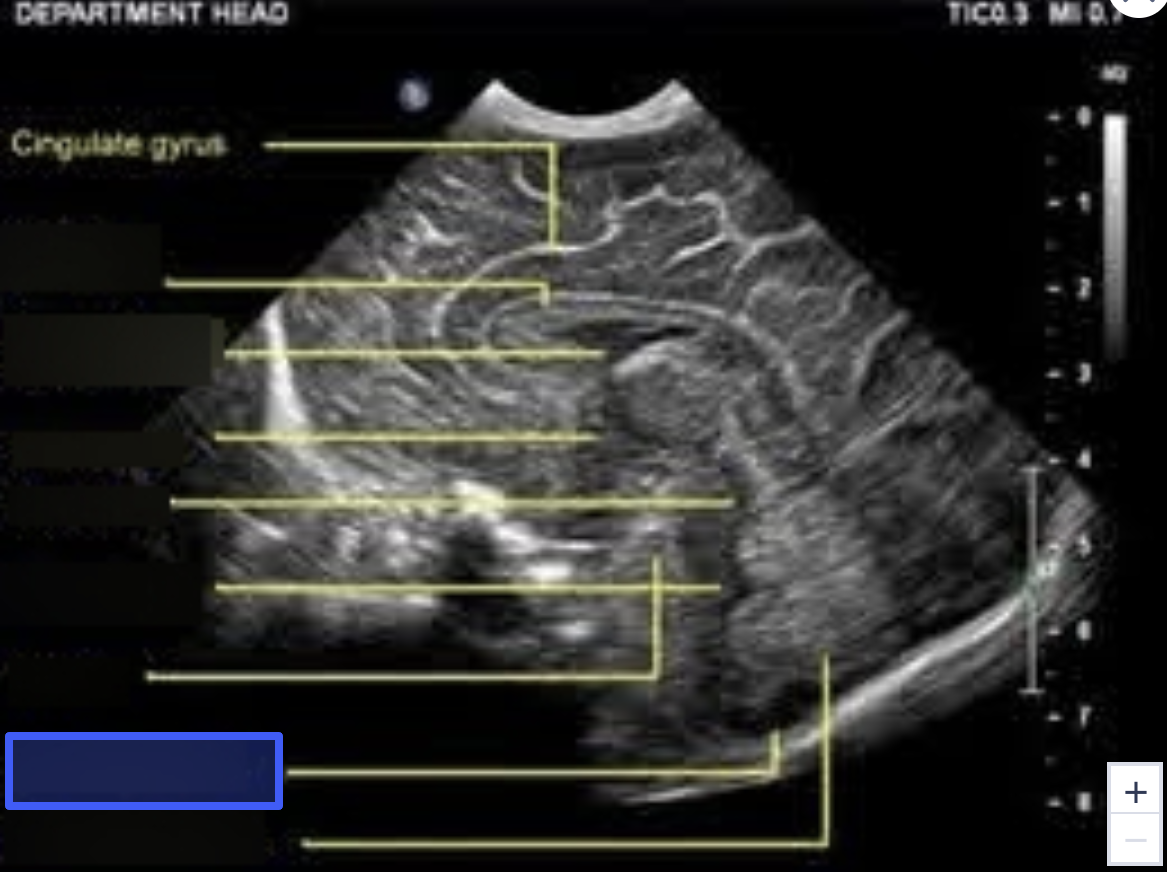

Sylvian Fissure

What is the highlighted structure?